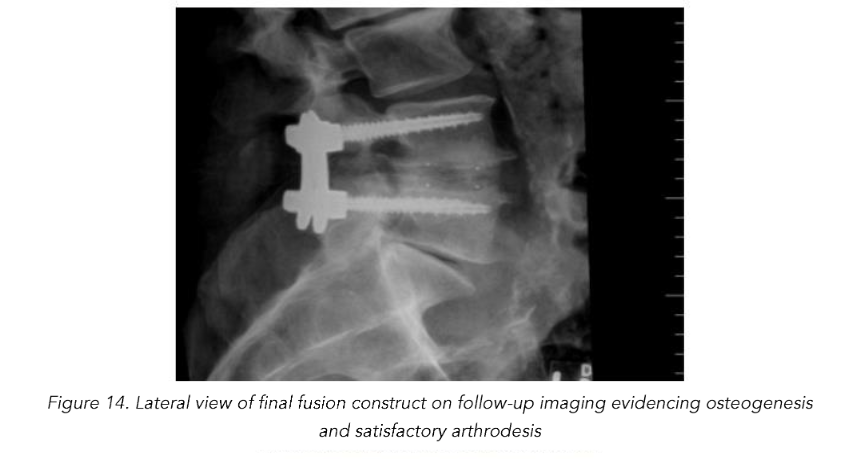

Total reduction of spondylolisthesis is performed by securing the rod to the most dorsal pedicle screw head (i.e., L5 seen in L4–5 spondylolisthesis) (Figure 10) and subsequently bringing the ventral pedicle screw head up towards the rod (Figure 11). This is done simultaneously bilaterally to reduce rotation and achieve total spondylolisthesis reduction thus restoring sagittal alignment. The advantages of this technique specifically arise from significant increases in the diameter of the neural foramen and spinal canal, and the larger surface area for fusion between adjacent vertebrae. The unique design of the PEEK Thompson MIS BoneBac TLIF device, with curved ends that correspond to the vertebral endplates, helps to facilitate reduction of the spondylolisthesis (Figures 10 and 11). Final tightening is performed, and the towers are removed allowing the paraspinous muscles to return to their normal anatomical position. Excellent long-term clinical outcomes and fusion rates using the MI-TLIF technique described have been achieved (Figures 13 and 14). More recently, but not within the patients covered in this data set, we began trialing augmented reality image guided navigation to place percutaneous pedicle screws in an effort to further reduce radiation exposure to both the patient and surgical team (Figure 15).

Almost all (18/19, 95%) patients achieved fusion of the lumbar spine confirmed by radiographic imaging on follow-up visits. One patient required repeat fusion due to posterior cage displacement complicated by adjacent segment disease. Six months after undergoing a primary L4-5 MI-TLIF, mild retropulsion of the interbody device was noted, but the patient denied any symptomatic manifestations. The patient presented 2 years and 6 months after the primary operation with severe neurogenic claudication when standing as well as shooting pains extending down the contralateral lower right limb. At this time, the patient was found to have significant central stenosis as well as concomitant adjacent segment stenosis at L2-3 and L3-4. Adjacent level stenosis was felt to be a continuation of the patient’s underlying degenerative disc disease leading to lumbar stenosis. This patient was re-treated 2 years and 7 months after the primary procedure with a repeat MI-TLIF at the index level (L4-5) and additional laminectomy and fusion at L2-3 and L3-4 due to progressive adjacent segment disease confirmed radiographically. The patient made an unremarkable recovery.